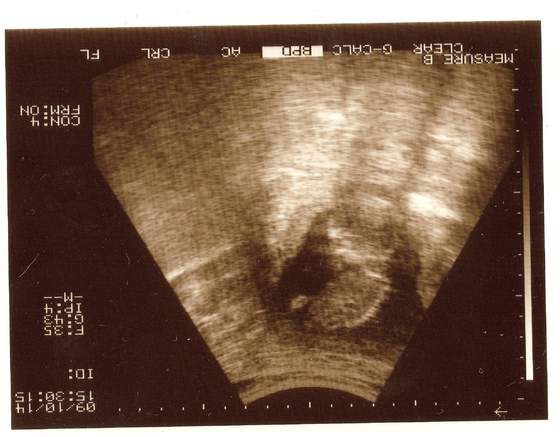

sandra -miałaś usg?? wklej zdjecie dzidziusia:-)